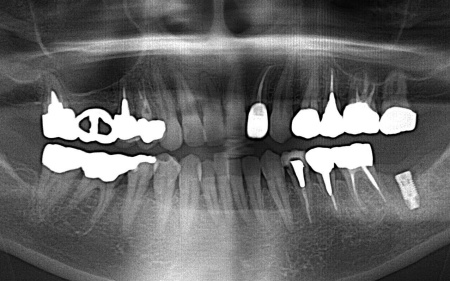

レントゲン撮影を行って詳しく調べたところ、歯根が縦方向に割れている「歯根破折」が疑われる状態です。

その後、歯科用CT撮影を行い、顎の骨の量や形、神経や血管の位置を立体的に確認しました。撮影したデータをもとに、インプラントを埋め込む位置や角度、深さについて事前に設計を行い、安全性と噛み合わせのバランスを考慮した治療計画を立てます。

抜歯後の骨の状態を確認しています。

インプラントの埋入設計をしました。

インプラント体と骨の結合を確認しました。